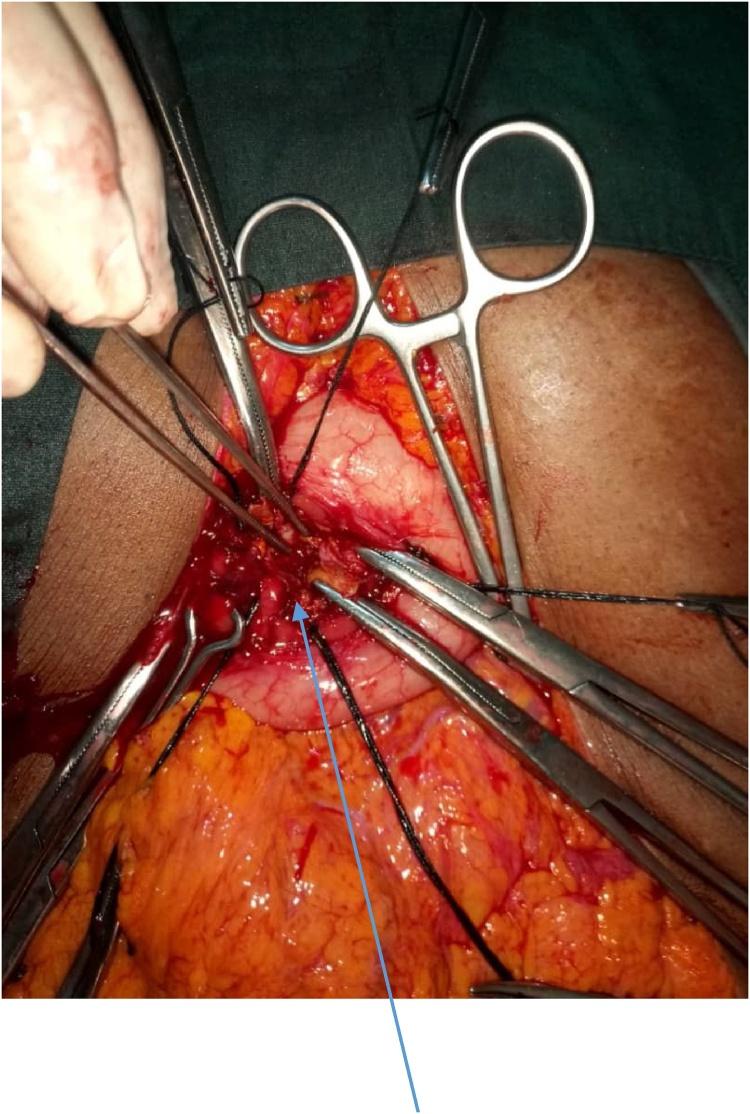

Two female patients aged 22 years and 65 years respectively, and an 11-year-old boy presented with giant pancreatic pseudocysts (>10 cm in diameter each) to our unit and were successfully managed. They all underwent exploratory laparotomy and cysto-gastrostomy with good outcome.

两名分别为22岁和65岁的女性患者以及一名11岁男孩因胰腺巨大假性囊肿(直径均>10 cm)前来我院就诊,并成功接受治疗。他们均接受了剖腹探查术和囊肿胃吻合术,效果良好。